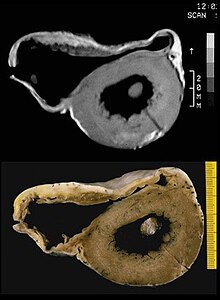

Biopsy[edit | edit source]

Transvenous biopsy of the right ventricle can be highly specific for ACM, but it has low sensitivity. False positives include other conditions with fatty infiltration of the ventricle, such as long-term excessive alcohol use and Duchenne or Becker muscular dystrophy.

False negatives are common, however, because the disease progresses typically from the epicardium to the endocardium (with the biopsy sample coming from the endocardium), and the segmental nature of the disease. Also, due to the paper-thin right ventricular free wall that is common in this disease process, most biopsy samples are taken from the ventricular septum, which is commonly not involved in the disease process.

A biopsy sample that is consistent with ACM would have > 3% fat, >40% fibrous tissue, and <45% myocytes.

A post mortem histological demonstration of full thickness substitution of the RV myocardium by fatty or fibro-fatty tissue is consistent with ACM.